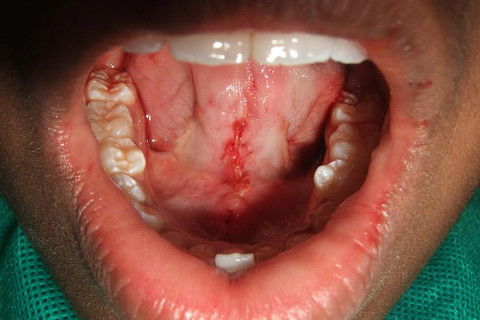

COM A SUTURA FOI UTILIZADO CAT GUT

REMOÇÃO DO FREIO